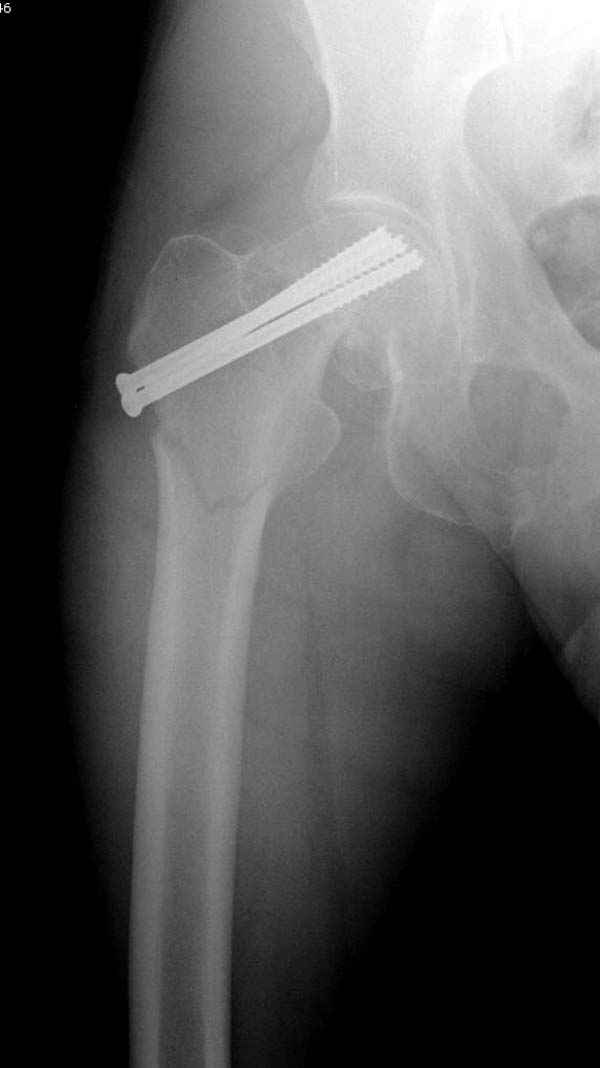

в течение первых 72 часов после перелома, остеосинтез тремя спонгиозными шурупами.

Профилактику дальнейшего раскола неполного перелома шейки провели тремя канюлированными шурупами.

На второй день после выписки упал дома. Снимки приложены. Коллеги рекомендуют удаление шурупа и вытяжение. Что делать?